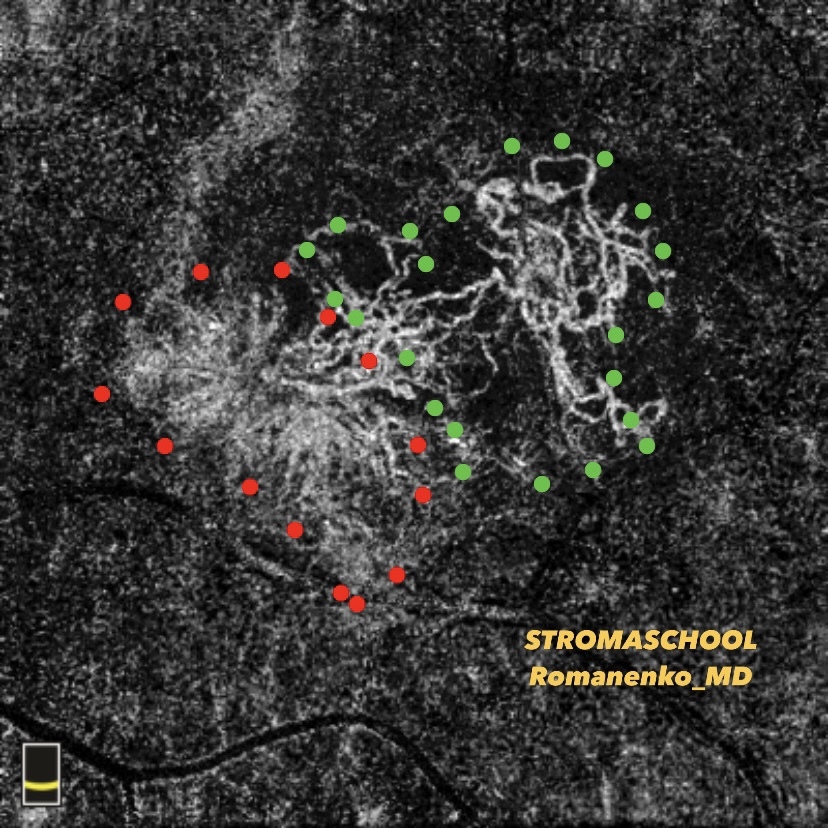

- все материалы (фото фундус камеры, сканы ОКТ взяты из личной практики и разобраны для Вас лично мной) - это ЧЕСТНО! А здесь только так!

- видео, сканы ОКТ с обозначениями, фото глазного с разбором на детали, аудисопровождение, текст и, конечно, ОБУЧАЩИЕ ТЕСТЫ